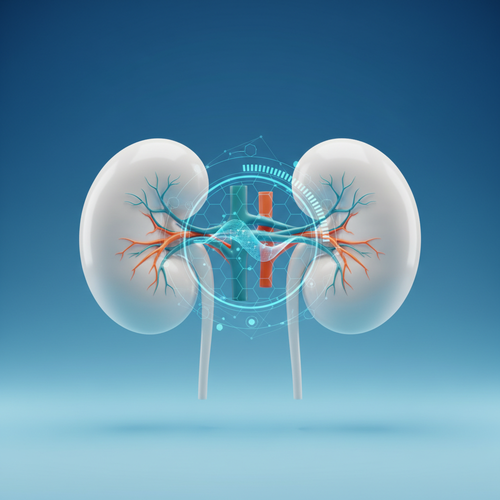

신장 질환: 소리 없이 찾아오는 위험 신호

신장! 우리 몸의 콩팥이죠.

왼쪽 신장은 왼쪽 옆구리 뒤쪽에

자리 잡고 있는데요,

이 신장에 문제가 생겨도

왼쪽 옆구리 통증이 나타날 수 있어요.

대표적인 신장 질환으로는

신우신염(신장 감염)이나 신장 낭종,

수신증(신장에 물이 차는 현상) 등이 있어요.

신장 기능이 저하되면

노폐물이 제대로 걸러지지 않아

몸 전체에 안 좋은 영향을 미치게 돼요.